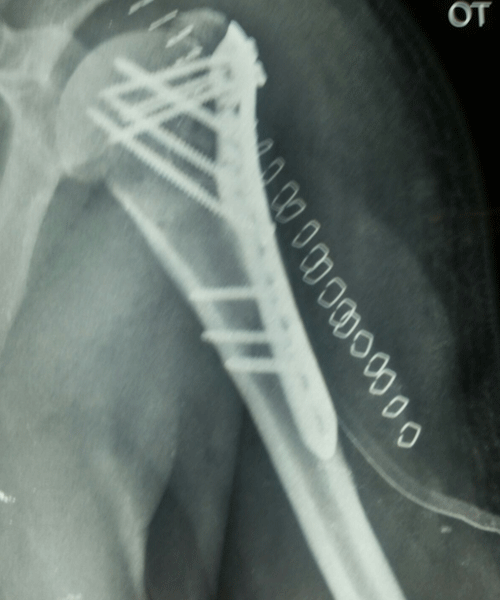

Case:18 Comminuted Fracture Upper Humerus

Female 65 years sustained fall in the house had displaced fracture of head of left Humerus with displaced fragment of greater tuberosity was treated with open deduction and philos plate fixation.

Pre-Op-Xray

Pre-Op CT Scan

CT Scan lateral

Post-Op Xray